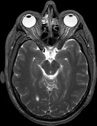

Visible Human male: Sectio transversalis 1107

NMR

Pd T1 T2